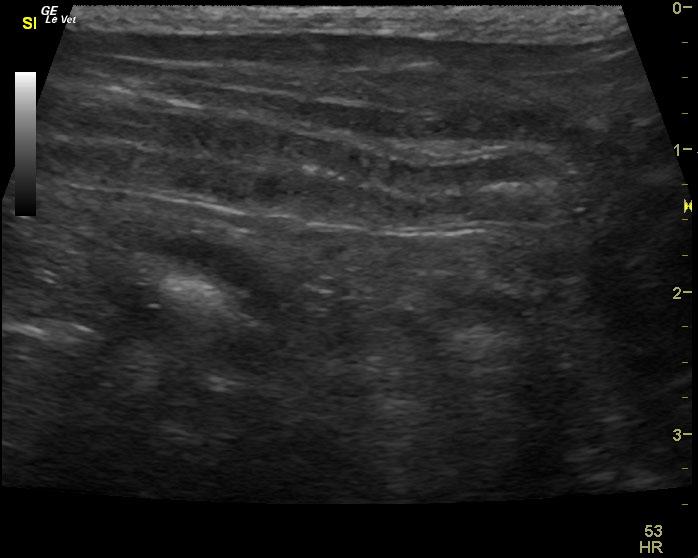

A 9 year old MN Maltese dog was presented for evaluation of progressive anorexia and soft feces. Physical examination and rectal palpation were both within normal limits. Fecal and urinalysis, CBC, serum biochemistry, cPl, and survey radiographs of the thorax and abdomen were all within normal limits.